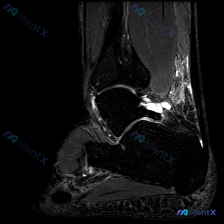

刚看到这个踝关节MRI的读片病例,整理了完整信息和分析思路分享给大家。 病例影像基础信息 这是踝关节矢状位T2加权压脂序列MRI,核心问题是图像中可见软组织液信号,我们来拆解分析: 影像学核心发现 1. 核心异常定位:距骨下方、跟骨上方的跗骨窦区域,存在明显信号异常 2. 跗骨窦内可见一个圆形/椭圆...